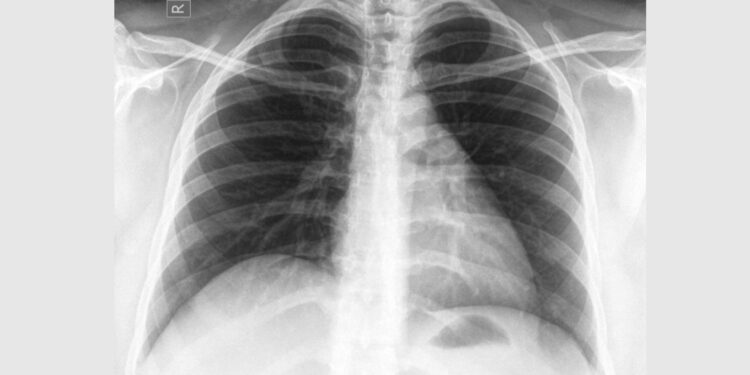

담배 안 피우는데 폐암?…”만성 폐질환 있으면 폐암 위험 3배”

비흡연자 6천명 대상 연구…”만성폐쇄성폐질환 환자는 위험 7배 넘게↑”

흡연 경험이 없더라도 만성 폐 질환 병력이 있는 경우 폐암 발병 위험이 3배 가까이 증가하는 것으로 나타났다.

삼성서울병원은 이 병원 폐식도외과 김홍관·이정희 교수와 서울아산병원 호흡기내과 지원준 교수가 이끄는 연구팀이 비흡연 폐암 환자들을 대상으로 연구를 수행해 이 같은 결과를 얻었다고 11일 밝혔다.

연구진은 2016∼2020년 삼성서울병원과 서울아산병원에서 비소세포폐암을 진단받은 3천명과 폐에 이상이 없는 대조군 3천명을 선정해 위험 요인을 정밀 분석했다. 양 집단은 모두 흡연 경험이 없는 비흡연자였다.

그 결과 비흡연자 폐암 발병의 가장 강력한 위험인자는 ‘만성 폐 질환 유무’인 것으로 나타났다.

비흡연 환자 중에서 폐결핵 등 폐 관련 질환 병력이 있는 경우 폐암 발병 위험이 대조군보다 2.91배 높았다.

특히 만성폐쇄성폐질환(COPD) 환자의 경우 폐암에 걸릴 위험이 7.26배까지 올라갔다. 연구진은 이러한 위험이 폐에서 계속되는 만성적 염증 반응 때문일 것으로 추정했다.

가족력도 폐암 위험을 높이는 데 기여하는 것으로 나타났다. 1촌 이내 가족 중 폐암 환자가 있는 경우 발병 위험이 1.23배 높았다. 이 중 형제자매가 폐암 병력이 있을 때 위험도는 1.54배로 커졌다.

또한 연구진이 폐암의 사회경제적 요인을 분석한 결과, 비수도권 거주자의 폐암 위험이 수도권 거주자보다 2.81배 높았다. 실업 상태인 경우에도 폐암 위험은 1.32배 증가했다. 연구진은 지역 간 산업 환경 차이나 의료 접근성 등이 이러한 결과에 영향을 미쳤다고 봤다.

병원에 따르면 한국을 포함한 동아시아에서 신규 폐암 환자의 절반 이상이 비흡연자로 보고되면서 흡연력 기준만으로는 이들의 발병 위험을 예측하고 데 한계가 있다는 지적이 제기돼 왔다.

지원준 교수는 “기존 흡연자 중심의 검진 체계를 넘어 비흡연자 고위험군을 선별할 수 있는 새로운 예방 및 치료 전략이 필요하다”고 강조했다.

김홍관 교수는 “비흡연자들은 상대적으로 폐 건강에 소홀하기 쉬운데, 담배를 피우지 않더라도 만성 폐 질환이 있거나 폐암 가족력이 있다면 정기 검진과 관리를 통해 폐암을 조기 예방하는 것이 좋다”고 말했다.

이번 연구는 호흡기 분야 국제학술지 ‘체스트(CHEST, IF=9.2)’ 최근 호에 게재됐다.